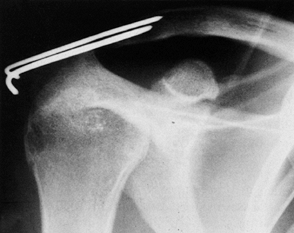

If closed technique is to be used, insert a 1/8-in.

or larger smooth Steinmann pin antegrade from the lateral edge of the

acromion to the joint. Then reduce the joint closed and, under

fluoroscopic guidance, insert the pin across the joint into the

clavicle.

Some authors prefer to open the joint for

debridement and reduction. Use a “saber cut” incision 5 cm or so in

length directly over the AC joint. Insert the pins retrograde from the

joint into the acromion and then into the clavicle after reduction of

the joint. Always bend the portion of the pin that protrudes through

the lateral acromion process to lessen the possibility of medial

migration (Fig. 78.10).![]() Figure 78.10. Figure 78.10.

Open reduction of the AC joint and stabilization of the joint with two

pins effectively reduced the fractured coracoid. Note that the distal

ends of the pins have been bent to prevent medial migration.

excessive abduction of the shoulder to prevent breakage or migration of

the pins. Rowe (155) recommends that abduction

motion be limited to no more than 40°. Remove the pins after 6 to 8

weeks and begin range-of-motion and strengthening exercises.